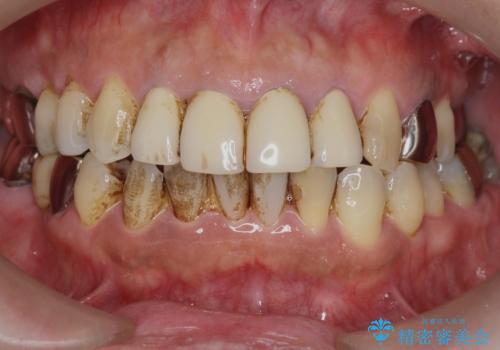

- 10数年前に治療した上顎前歯のクラウンをやり替え、審美性を回復したいと希望され来院されました。

X線写真より問題のなかった根管治療は行わず、クラウンを除去し仮歯でを装着したのちジルコニアクラウンを製作していきます。

茶しぶの目立つ下顎前歯はPMTCを行うことで歯の自然な白さを回復しました。